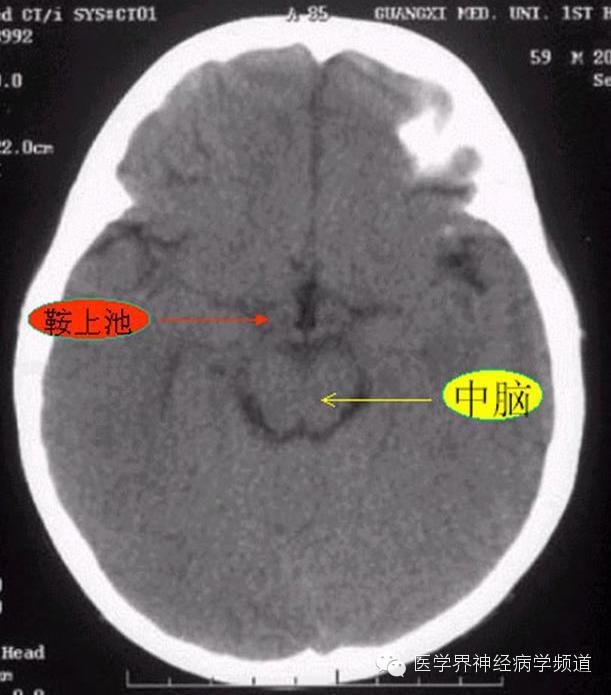

神经影像CT读片step by step